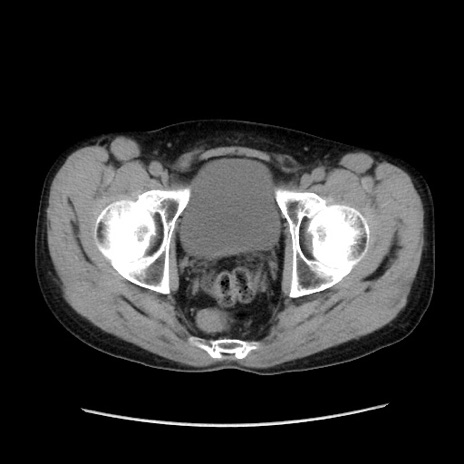

症例37(横断像)

【症例】40歳代 男性

【主訴】腹痛

【現病歴】4時間ほど前に電車に乗車中に臍部上より腹痛出現。徐々に増悪し起立困難となり、救急外来受診。生ものは数日食べていない。今朝お雑煮を食べた。

【身体所見】BT 36.8℃、BP 117/84mmHg、HR 91/min、SpO2 97%、苦悶様、腹部:臍上部広範囲圧痛あり、反跳痛±

【データ】WBC 8100、CRP 0.03